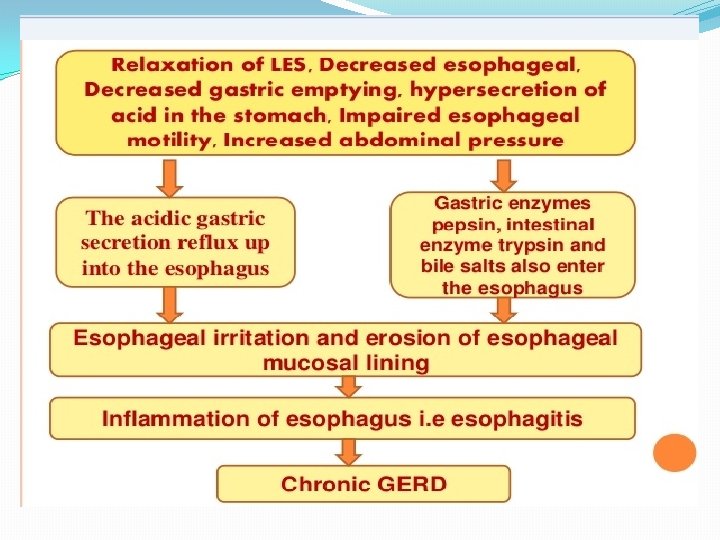

Pathophysiology Antireflux barrier: *lower esophageal sphincter (LES) *the crura of the diaphragm *gastroesophageal junction anatomy

The mechanisms involved in the pathogenesis of GERD are multiple and include: 1. impaired LES resting tone 2. increased number of transient LES relaxations (TLESR) 3. Gastric distention (delayed gastric emptying, large fatty meals) can significantly increase the rate of transient LES relaxations) 4. hiatal hernia (promoting lower oesophageal sphincter dysfunction)

5. Impaired oesophageal acid clearance (this process involves peristalsis as well as the swallowing of salivary bicarbonate) lead to prolonged acid exposure of the mucosa. 6. increase intra-abdominal pressure (straining, obesity, coughing, wheezing).